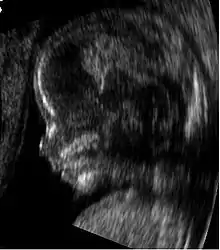

يسمح تخطيط الصدى الطبي بفحص الأعضاء الحوضية عند الإناث (خاصة الرحم، والمبيضين، وقناتي فالوب)، بالإضافة إلى المثانة، وملحقات الرحم، ورتج دوغلاس. يُستخدم في هذا الإطار مسابير خاصة للفحص عبر جدار الحوض ذات سطح منحنٍ وقطاعي، بالإضافة إلى استخدام المسابير المخصصة كالمسبار المهبلي.

صورة لمقطع عرض شاشة.